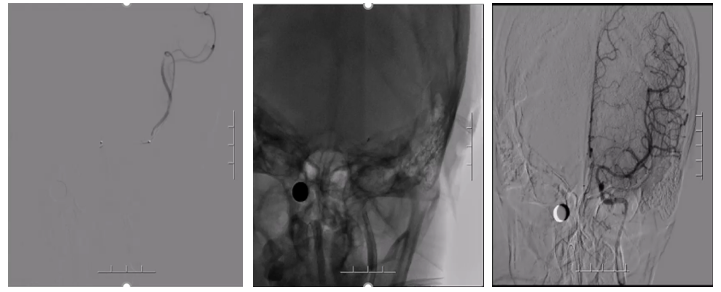

病历夹什么径技·第151期|串联营病历夹:京广连营_https://www.jmylbn.com_新闻资讯_第75张

病历夹什么径技·第151期|串联营病历夹:京广连营_https://www.jmylbn.com_新闻资讯_第76张

病历夹什么径技·第151期|串联营病历夹:京广连营_https://www.jmylbn.com_新闻资讯_第77张

<<滑动查看下一张图片>>

• 左侧椎动脉造影见基底动脉起始处闭塞。

• 微导管造影,见基底动脉尖及左侧大脑后动脉显影不良,考虑栓塞。

• 基底动脉近端打开支架,支架形态尚可,局部发白,左侧大脑前动脉P1段栓塞。

• 支架取栓取出一小块栓子,造影见基底动脉起始处重度狭窄。

• 狭窄处予球囊扩张成形,球扩后造影见基底动脉狭窄有所改善。

• 微导管送至左侧大脑后动脉P2段,造影确认真腔后,释放支架,并支架取栓1次。

• 血栓成功取出,基底动脉侧位造影,左侧大脑后动脉再通。

• 正位造影,左侧大脑后动脉再通,无血栓逃逸,基底动脉狭窄改善,未回缩,前向血流正常,观察后结束手术。